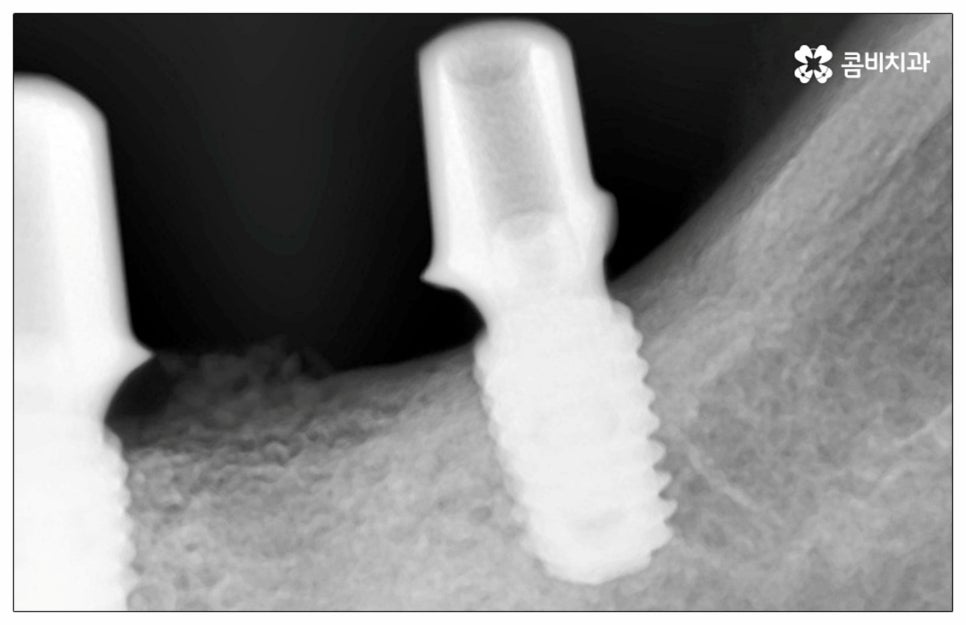

이때 추가 수술은 비급여 항목으로 건강보험임플란트 대상에서 제외되니 이에 대해서도 꼼꼼하게 살펴보시고 정밀 검진 후 담당 의료진과 자신의 상황에 대해서 충분하게 상담해 보시길 권유드리고 있습니다. 추가 수술의 대표적인 예로는 뼈이식 수술이 있는데요. 이것은 임플란트를 식립할 때 바탕이 되는 잇몸뼈의 높이나 폭, 밀도 등이 부족하다면 먼저 이를 보충해 주고 나서 임플란트를 심어주는 과정을 의미하며 같은 이유로 식립 성공률이나 장기적인 안정성을 높이기 위해 꼭 필요한 사전 처치, 즉 상악동 거상술 및 치주 질환 관련 수술 등을 먼저 해야 한다면 이 역시 추가 수술의 범주로 들어가니 자신의 상황에 대해서 상세하게 알아보실 필요가 있어요.

많이 대중화 되었다고 해도 임플란트 수술 자체가 술자의 숙련도에 크게 영향을 받는 복잡하고 고난도의 진료인 것은 틀림이 없기 때문에 담당 의료진이 해당 분야 임상 경험이 풍부한지, 뛰어난 기술력과 노하우를 가지고 있는지 꼼꼼하게 체크해 보실 필요가 있어요. 특히 노년층의 경우 당뇨, 고혈압 등 만성 질환을 앓고 있는 경우가 많아 혹시 상시 복용하고 있는 약이 있는지, 현재 환자 개개인의 상태는 어떤지, 사전 처치가 필요한 부분은 없는지 등등 수술 조건을 좀 더 까다롭게 평가한 후 환자분들과 이에 대해 충분히 상담하고 맞춤형 치료 계획을 세워 진행해야 하며 이를 위해 3D CT 와 같은 디지털 검진 장비를 통해 구강 내부 구조를 면밀하게 살피고 방대한 임상 데이터를 축적한 정품 임플란트 재료를 이용하여 연령이나 회복 정도를 살펴보면서 체력적 부담을 줄이는 방향으로 무리하지 않게 식립하는 것이 무엇보다 중요하다고 할 수 있습니다.